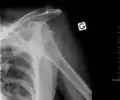

Dislocated shoulder

Anterior dislocation of the left shoulder.